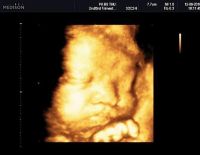

Tổng quan về kỹ thuật siêu âm 4D và những vấn đề liên quan

Siêu âm 4D là phương pháp chẩn đoán hình ảnh hiện đại, phổ biến trong lĩnh vực y học hiện nay. Kỹ thuật giúp quan sát trực tiếp các hoạt động của thai nhi, đồng thời hỗ trợ phát hiện những dị tật sớm ở...